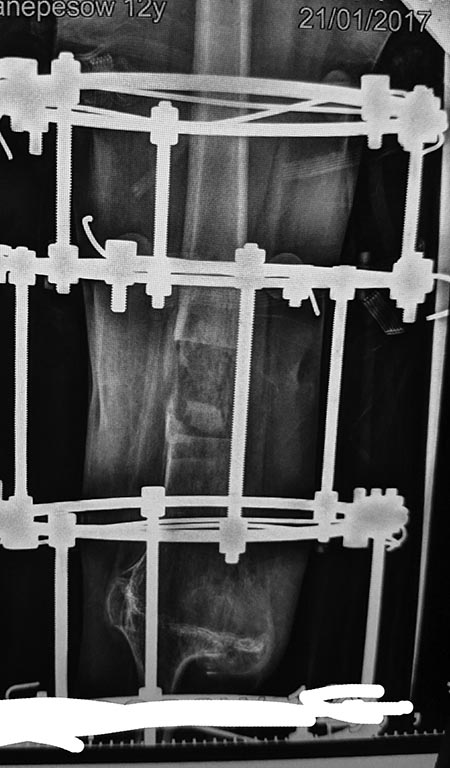

наложен аппарат бедро -голень и остеотомия бедра

Для более конкретных советов нужны фото и рентгенограммы.

Снимки

|

... да, дорогой, Ниязов Нияз, на бедре спицы могут натворить дел. Сориентируйтесь, пожалуйста, по прилагаемому атласу. Там все просто: выберите язык - кликните index.html - откроется сам атлас - кликните Атлас - выберите сегмент (ну, бедро, вестимо) - необходимые уровни.